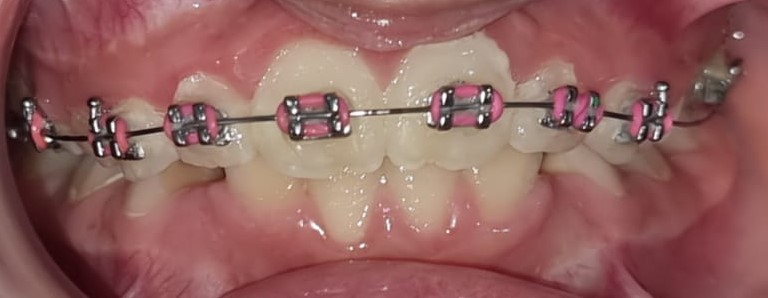

58) Niharika – After phase 1 with lower canine extractions – phase 2 has started- Treatment is completed